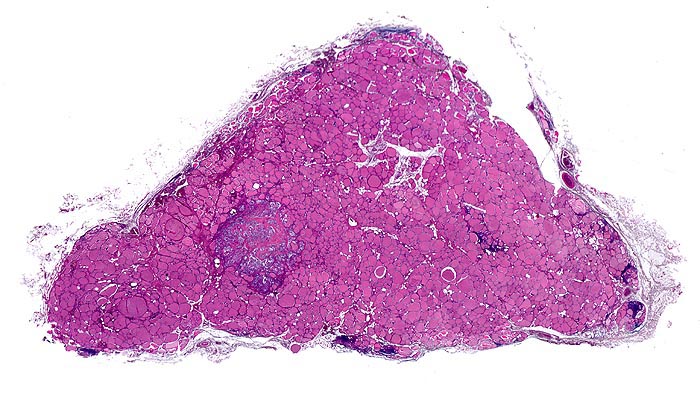

Makroskopisch imponieren sporadische Tumoren als solitäre, scharf begrenzte, manchmal gekapselte grauweisse Knoten mit rauher Oberfläche. Bei familiären Karzinomen finden sich häufig bilaterale multiple grauweisse unscharf begrenzte Herde und eine C-Zell Hyperplasie der Schilddrüse.

• Mehrere, unscharf begrenzte, unbekapselte Tumorknoten mit desmoplastischem Stroma in ansonsten unauffälligem Schilddrüsenparenchym.